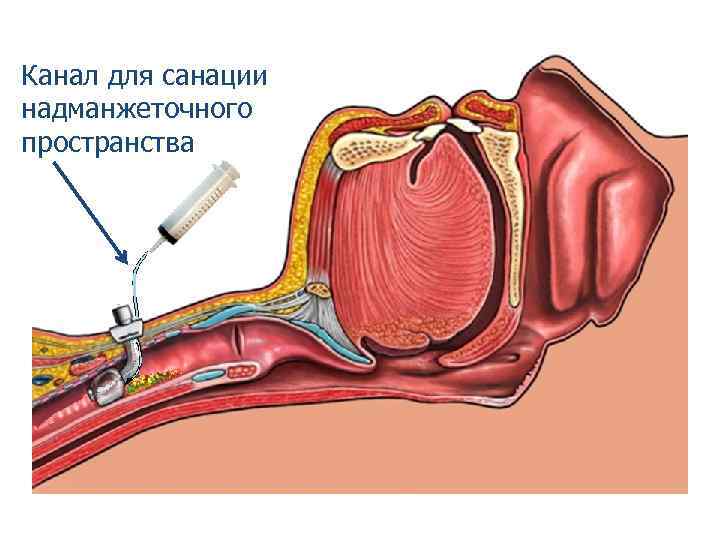

Санация надманжеточного пространства Muscedere J, et al. Crit Care Med 2011

Санация надманжеточного пространства Muscedere J, et al. Crit Care Med 2011

Профилактика и лечение инфекционновоспалительных изменений гортани и верхних отделов трахеи Дренаж надманжеточного пространства Portex

Профилактика и лечение инфекционновоспалительных изменений гортани и верхних отделов трахеи Дренаж надманжеточного пространства Portex

Канал для санации надманжеточного пространства

Канал для санации надманжеточного пространства